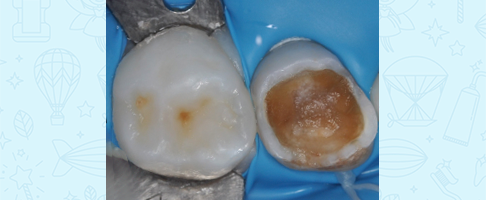

Лечение кариеса, восстановление зуба коронкой

Лечение кариеса молочного зуба, восстановление коронкой и герметизация фиссур с применением закиси азота

Лечение кариеса и пульпита молочных зубов во сне, восстановление коронками

Лечение пульпита молочного зуба, восстановление коронкой

Лечение пульпита молочного зуба, восстановление коронкой

Лечение пульпита молочного зуба, восстановление коронкой